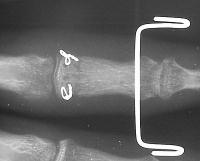

Intraoperative fixation and motion: Initial attempts of micro screw fixation were not successful, and wire cerclage was used: